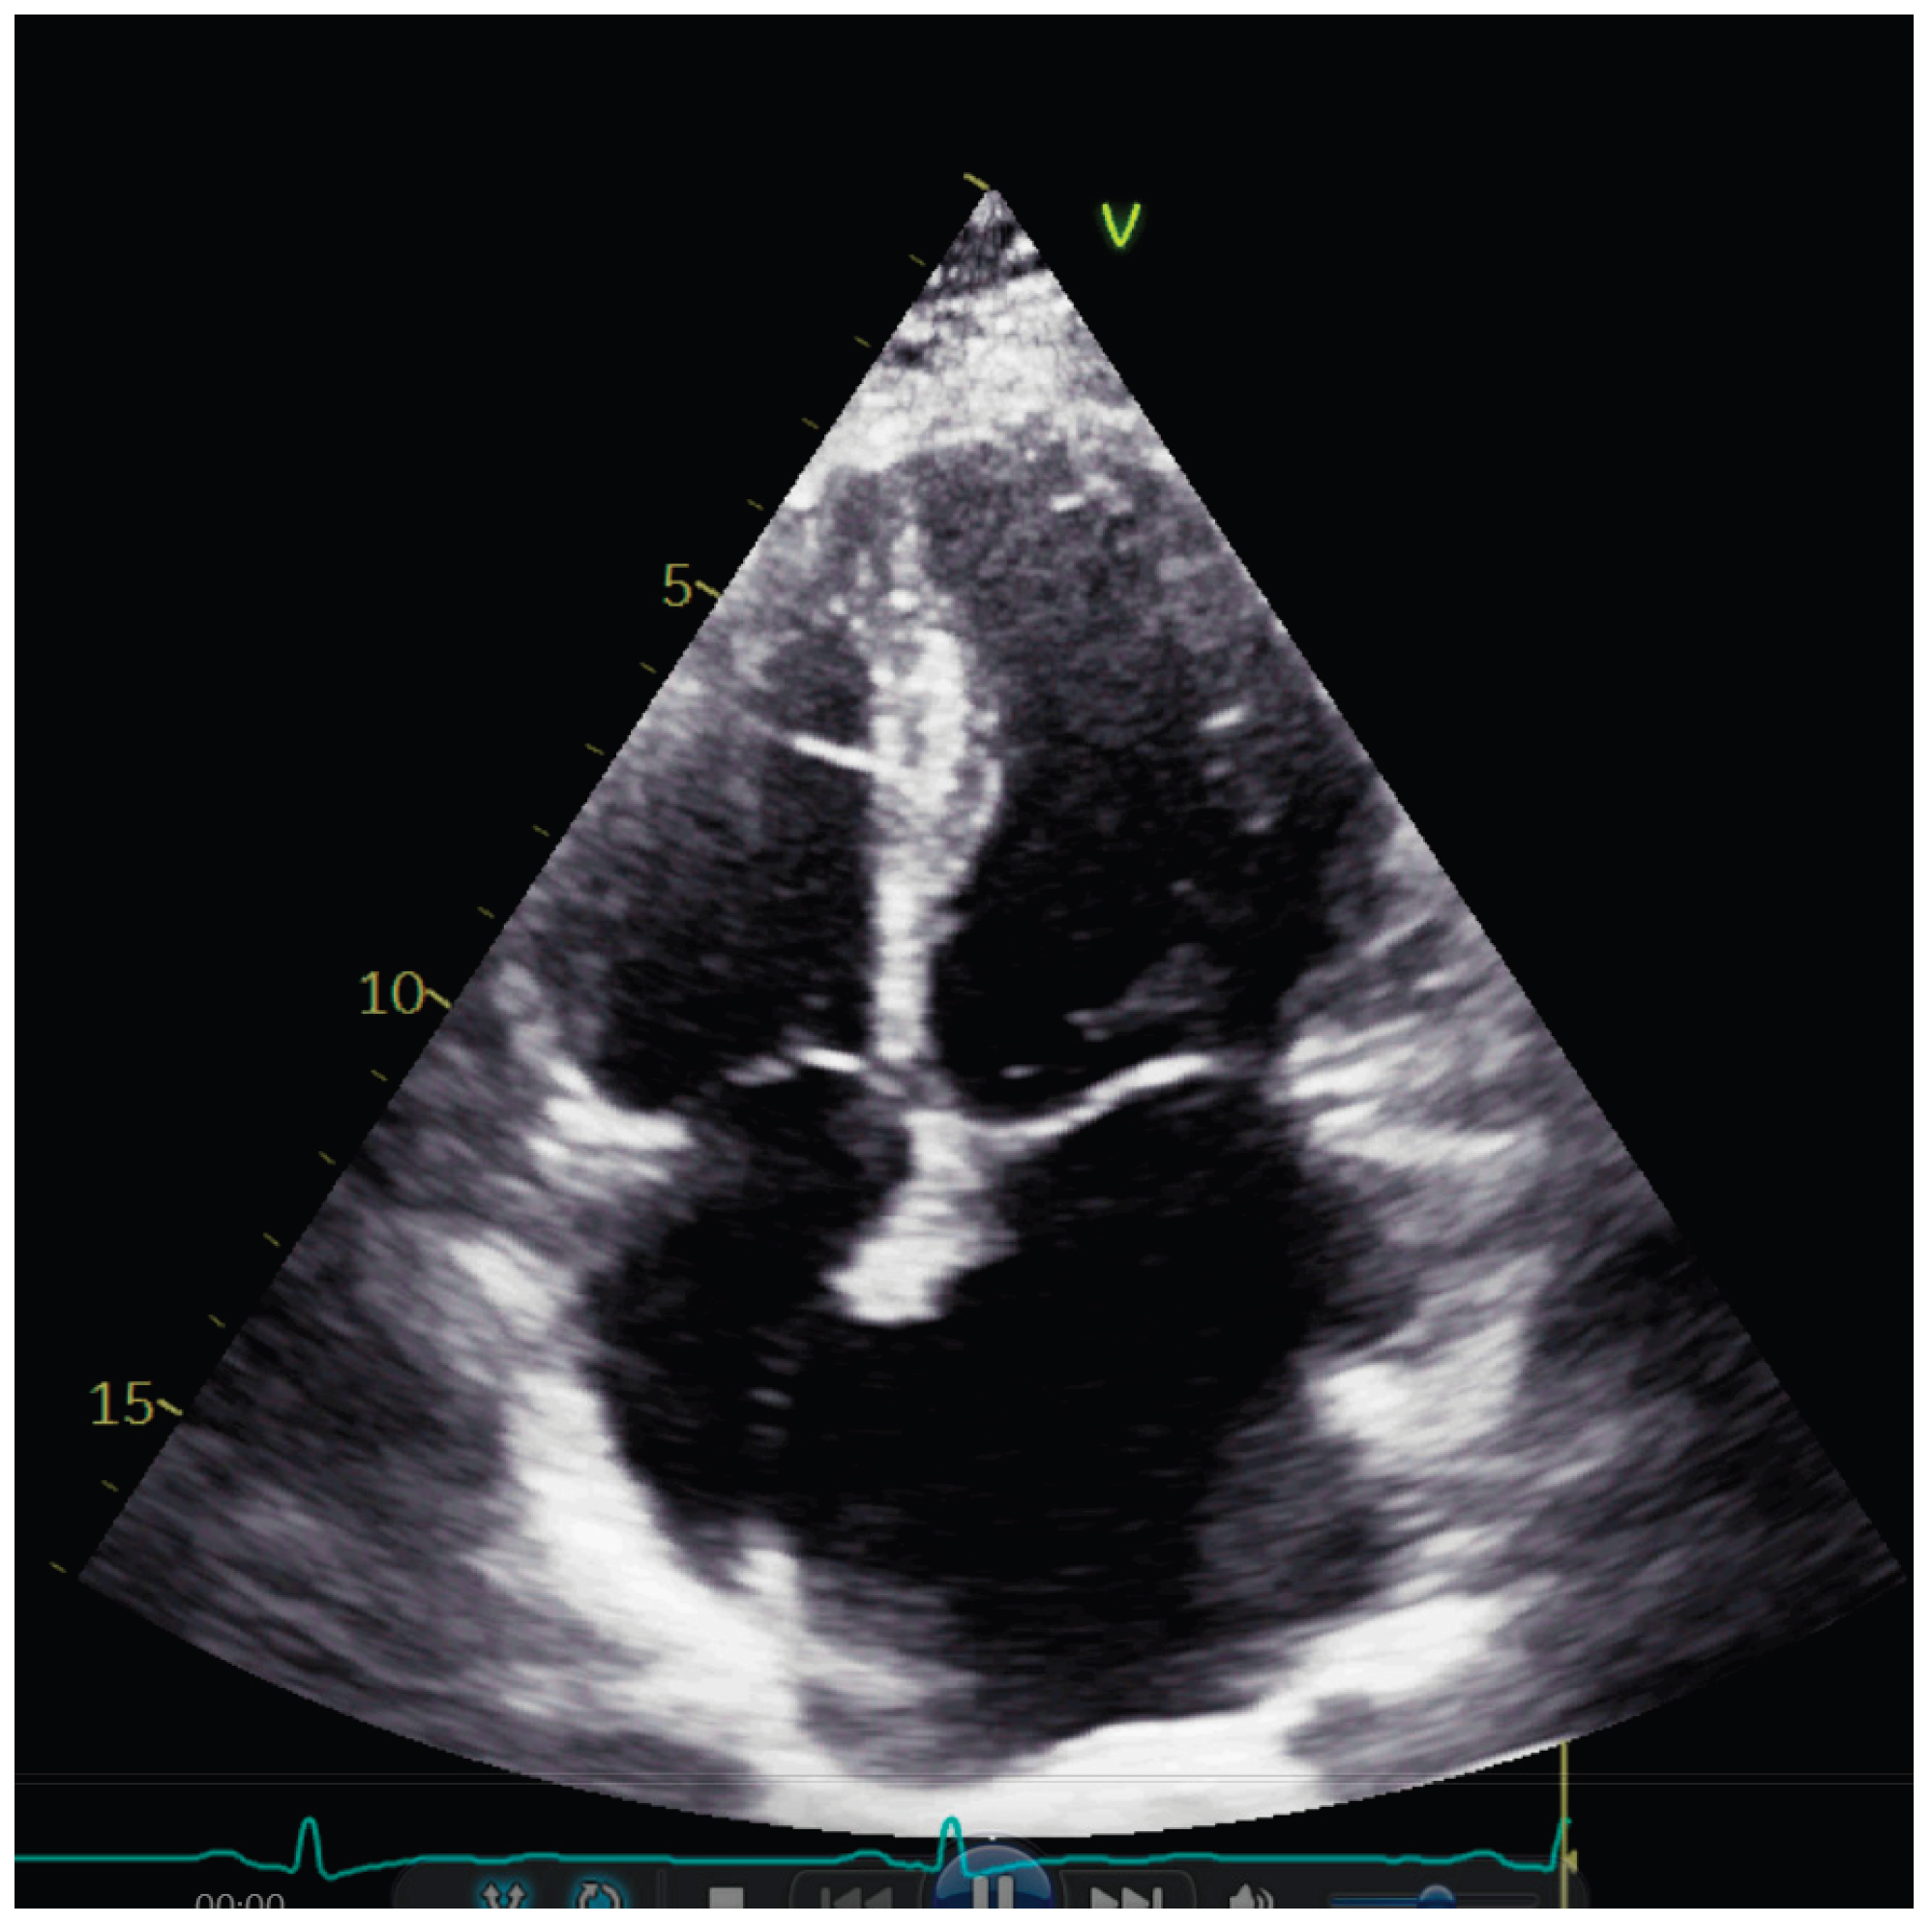

Transthoracic echocardiography showed normal diameters and volumes of the left ventricle. Interventricular wall thickness (IVWT) was within the normal ranges, respectively 8 mm. Transmitral Doppler showed a restrictive filling pattern with elevated E/A ratio and shortened deceleration time, consistent with impaired diastolic compliance. Extreme left atrium (LA) dilatation was observed, with the volume of 134 mL/m2. (Figure 1)

Figure 1. Apical four chamber image showing severe dilatation of the left atrium.